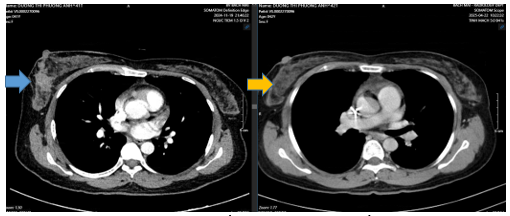

- CT ngực, bụng: Chưa phát hiện bất thường

Hình 5: Hình ảnh CT ngực 13 chu kì điều trị phác đồ TCHP- HP u vú phải đã cắt ( mũi tên xanh) không phát hiện hạch, khối bất thường trên CT ngực